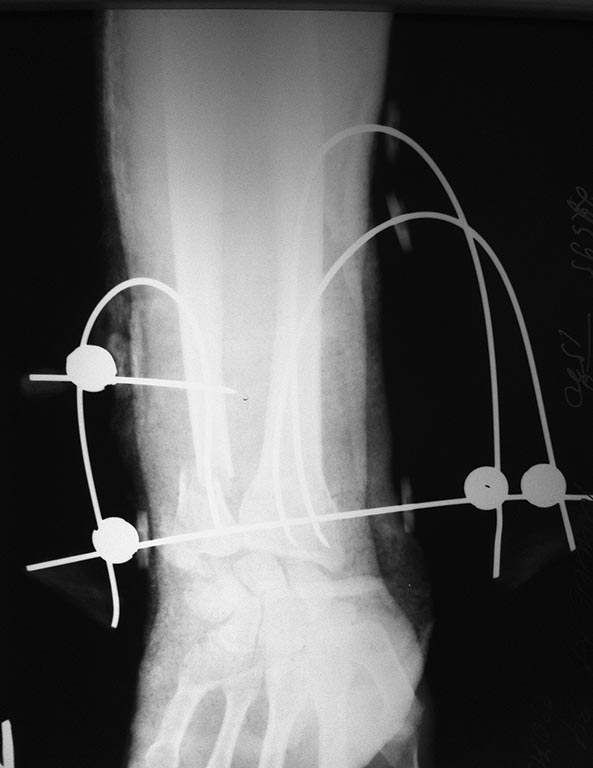

[Ortho] Остеосинтез н/3 предплечья

Р-граммы

Имя     : image (2).jpg